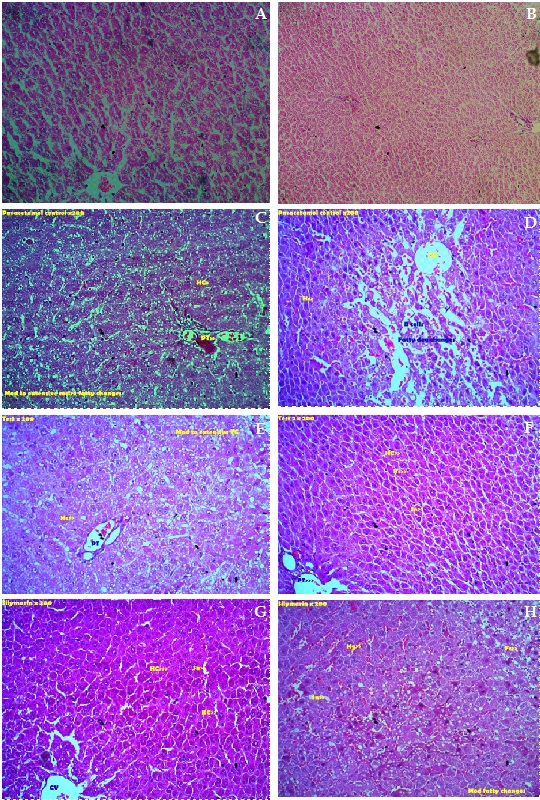

The objective of this study was to explore the hepatoprotective activity of fruits of Garcinia pedunculata in paracetamol-induced liver toxicity in rats. Paracetamol-induced hepatotoxicity was evaluated by an increase in serum transaminases and alkaline phosphatase activity. Histopathological observation showed extensive disturbance in the liver cytoarchitecture in comparison to normal control liver sections. Pre-treatment with aqueous extract of fruits of G. pedunculata prevented the paracetamol-induced increase in serum transaminases, alkaline phosphatase and histopathological changes. Based on the above observation it can be concluded that G. pedunculata pretreatment exhibited significant hepatoprotective activity against paracetamol-induced hepatotoxicity.